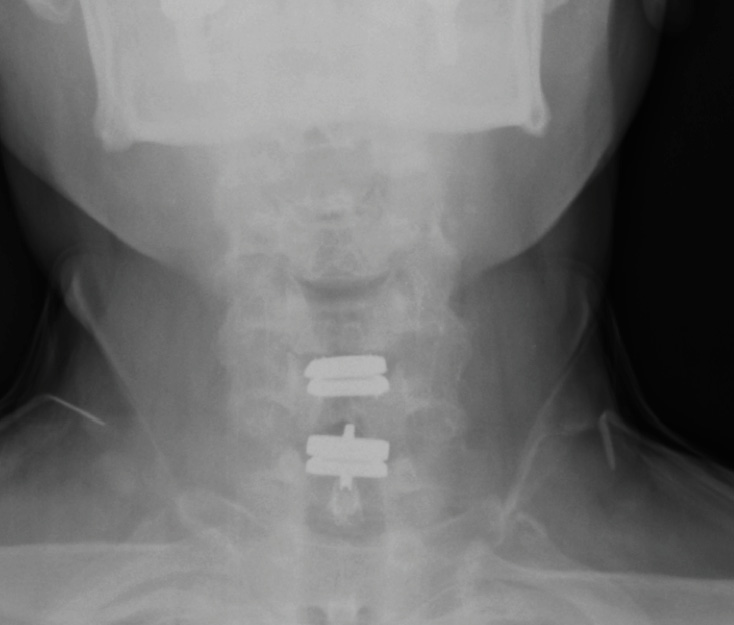

The patient’s symptoms have completely resolved. The x-rays in Figure 8 were taken at the first post-op visit at 2 weeks.